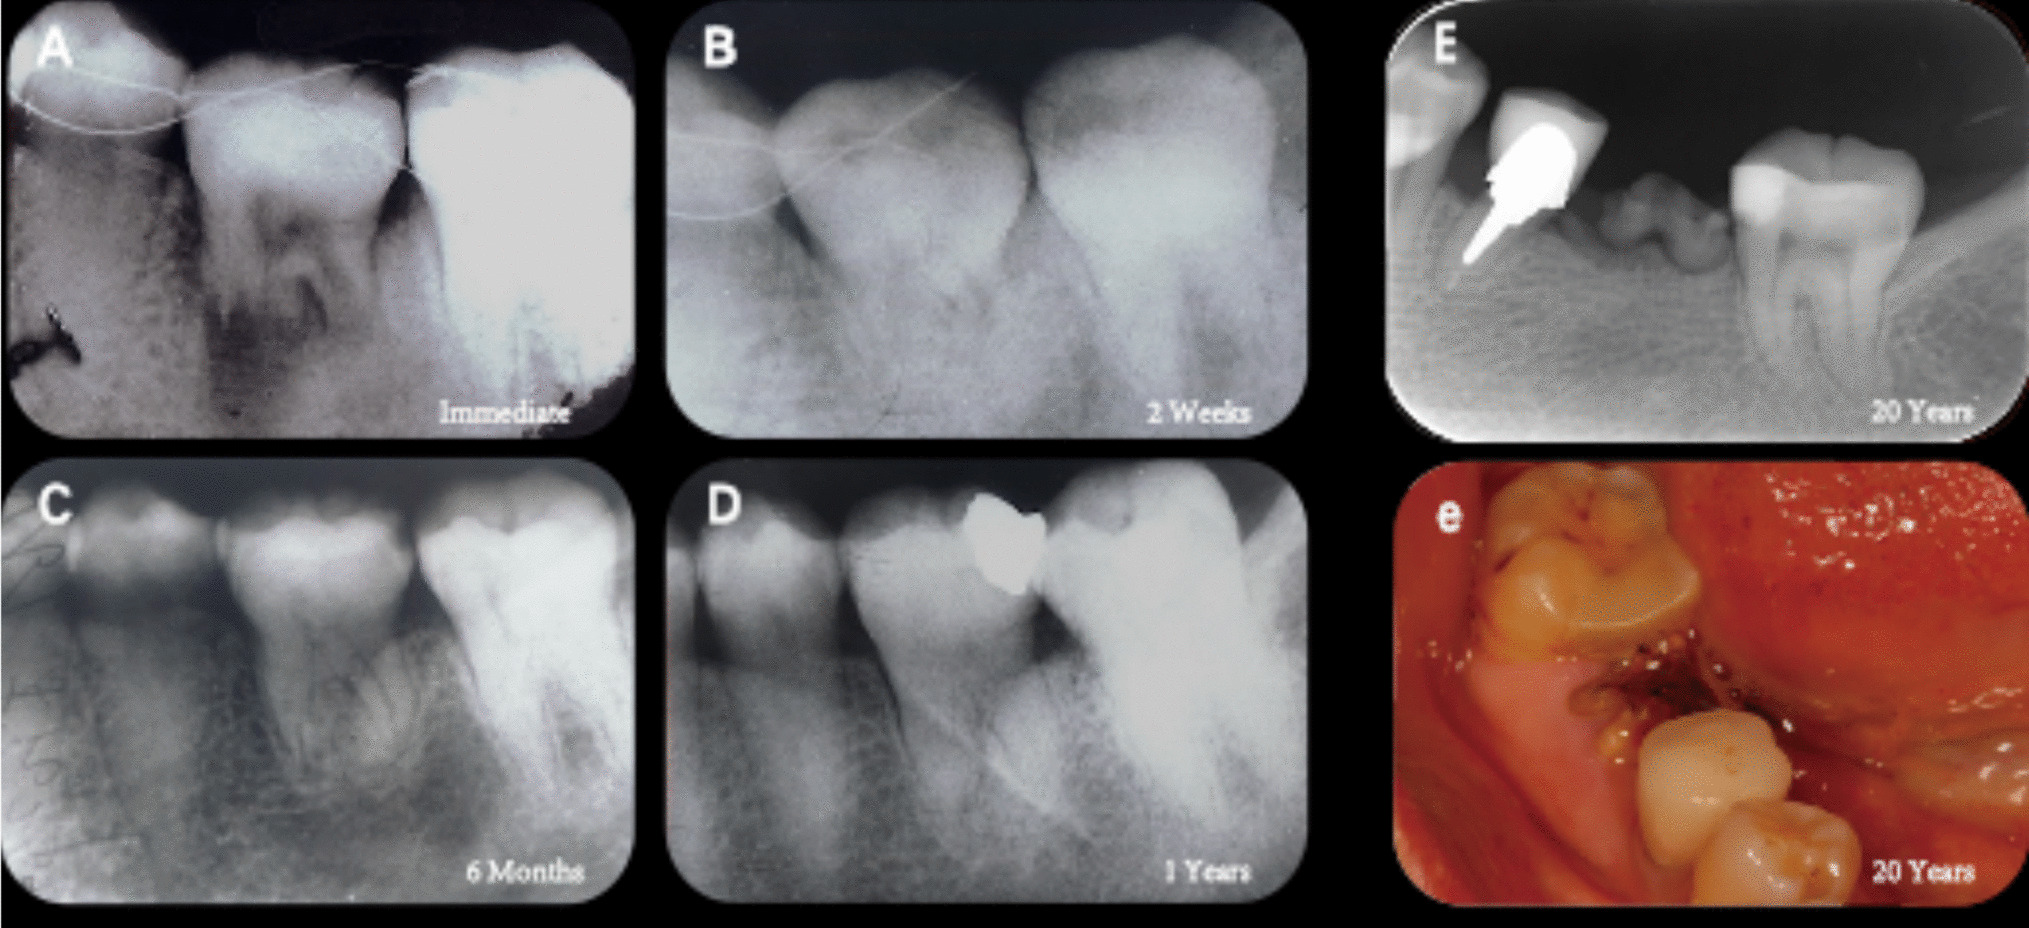

A follow-up examination was conducted six weeks later, during which the patient reported no signs of infection were observed in the region. The transplanted teeth remained stable, and gingival tissue exhibited healthy healing without redness or swelling. Although initial gingival healing was observed, tooth mobility remained high, so the planned endodontic treatment was postponed. After twelve weeks, stability improved compared to six weeks post-surgery, with no looseness or percussion pain. Radiographic evaluation indicated initial periodontal healing with no space between the distal surface of the root and surrounding bone (Fig. 12B). One year after surgery, integration of the transplant with adjacent dentition was confirmed: there were no gaps or percussion pain present, and gingival tissue appeared healthy and firmly attached. Radiographs showed that the root canal of the transplanted tooth had closed and calcified without inflammatory infiltration at its apex (Fig. 12C). Consequently, we decided against performing endodontic treatment while maintaining long-term follow-up observation.

Fig. 12

A six weeks postoperative (sparse osteogenesis and a 1 mm gap between the transplanted root and alveolar bone) (B) twelve weeks postoperative (ongoing bone remodeling with a reduced apical gap) (C) one year postoperative (satisfactory periodontal healing with a normal ligament space, calcified root canal, visible bony contour)